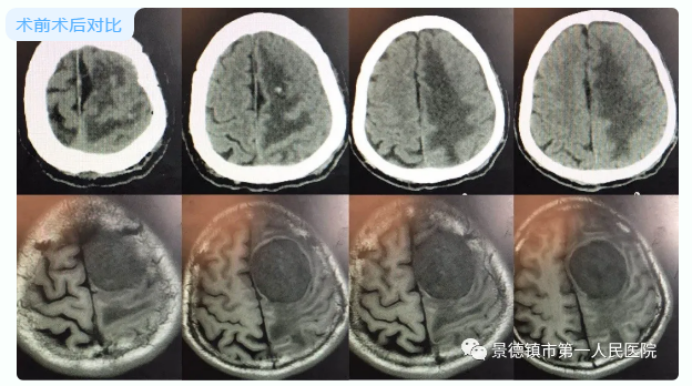

日前,市一院神经外科率先在全市引进手术GPS技术,成功为一巨大脑膜瘤患者行肿瘤摘除术,患者已痊愈出院。此类大脑镰旁巨大肿瘤手术该科室已成功开展10余例。

患者章某,男,62岁,反复头疼,头晕10余年伴右侧肢体麻木1年入院,查体发现右侧肢体肌力IV级。颅脑MRI提示:左侧顶叶巨大占位,诊断为大脑镰旁脑膜

患者前往多家医院,均被告知手术风险极大,未予以治疗。家属焦急万分,辗转就诊于我院神经外科。科室主任余兆祥及胡志方、张熙赟医师等人于3月20日在全麻下对患者进行手术治疗,术中利用导航系统实时定位引导手术操作,快速、精准、顺利地将肿瘤摘除,术后患者症状明显缓解,于3月30日痊愈出院。